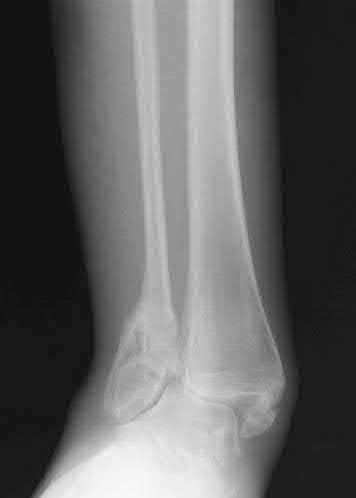

A 25-year-old male sustains an ankle fracture dislocation and undergoes open reduction and internal fixation. He returns to clinic five months following surgery complaining of continued ankle pain and instability with weight bearing. His immediate post-operative AP radiograph is seen in Figure A. Which of the following could have prevented this patient from developing persistent pain?

The patient presents with continued ankle pain and instability following open reduction and internal fixation. The radiograph in figure A demonstrates inadequate restoration of fibular length, likely leading to continued tibiotalar instability.

Illustration A demonstrates fibular malreduction with dislocation of the fibula anterior to the tibial incisura. Illustration B shows a comminuted fibula fracture along with a measurement of length from an intact fibula. The arc from the lateral process of the talus to the peroneal groove of the distal fibula is known as the "dime" sign and should remain unbroken if fibular length has been restored. Illustration C demonstrates the use of a push-pull screw and lamina spreader to regain length intraoperatively for a comminuted fibula fracture.

Chu and Weiner review management of malunions of the distal fibula. The authors state that restoration of fibular length, alignment and rotation leads to reduction of the talus, provides a buttress to talar motion in the setting of an incompetent deltoid, and allows the syndesmotic ligaments to heal at the appropriate tension.